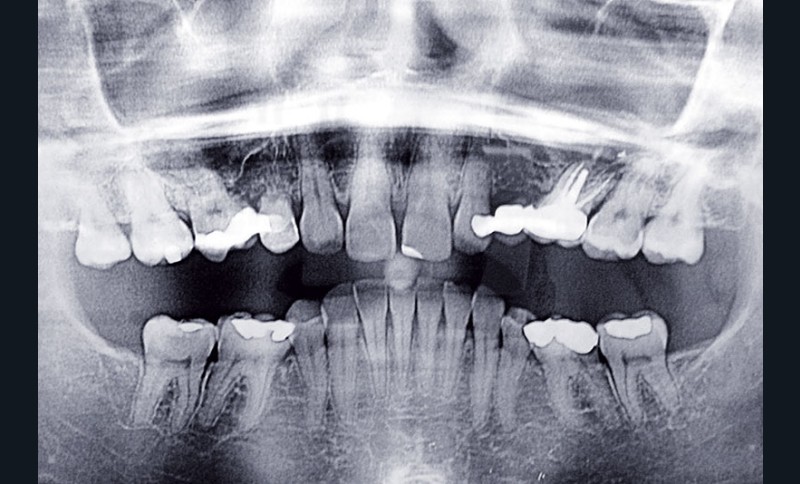

La patiente, âgée de 30 ans, présente des agénésies multiples : 12, 22, 14, 15, 24, 25, 35 et 45 (fig. 1 à 3).